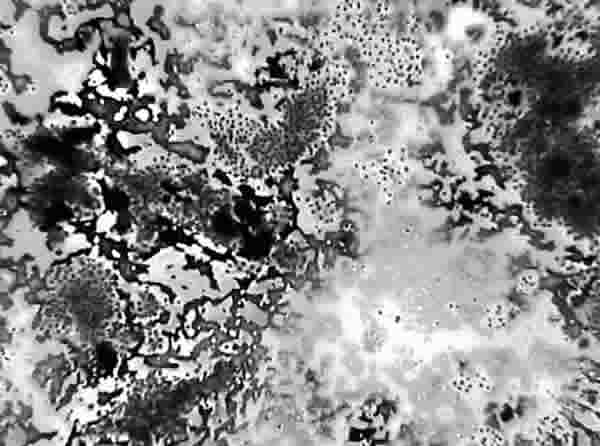

Fig. 7 PAAF de Tiroides. Proliferación folicular "indeterminada". Giemsa-QCA. x100. Grupos foliculares numerosos y coloide. Tejido: Hiperplasia nodular tiroidea con áreas adenomatosas.